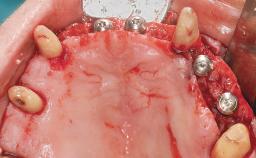

A 63-year-old male patient was referred for a consultation and treatment of partial edentulism in the maxilla. The patient presented with residual anterior teeth and declined a partial removable prosthesis. He reported that the maxillary posterior teeth had been extracted due to mobility and periodontal disease two months before the consultation. The patient’s chief complaint was that his residual maxillary teeth were mobile and that he was unable to chew. The patient’s desire was a stable and comfortable fixed maxillary rehabilitation. The patient was a light smoker (fewer than 10 cigarettes/ day), and his medical history was without significant findings. He was not on any regular medication at the time of consultation. The extraoral examination revealed a normal physiognomy with a correct distribution of the facial thirds. The patient presented a low lip line, and the transition line between teeth and soft tissues was not exposed during a forced smile.

| # of Implants | 6 |

| Type of Implants | One-Piece |

| Bone Augmentation | Horizontal|Simultaneous |

| Augmentation Materials | Xenogenous |